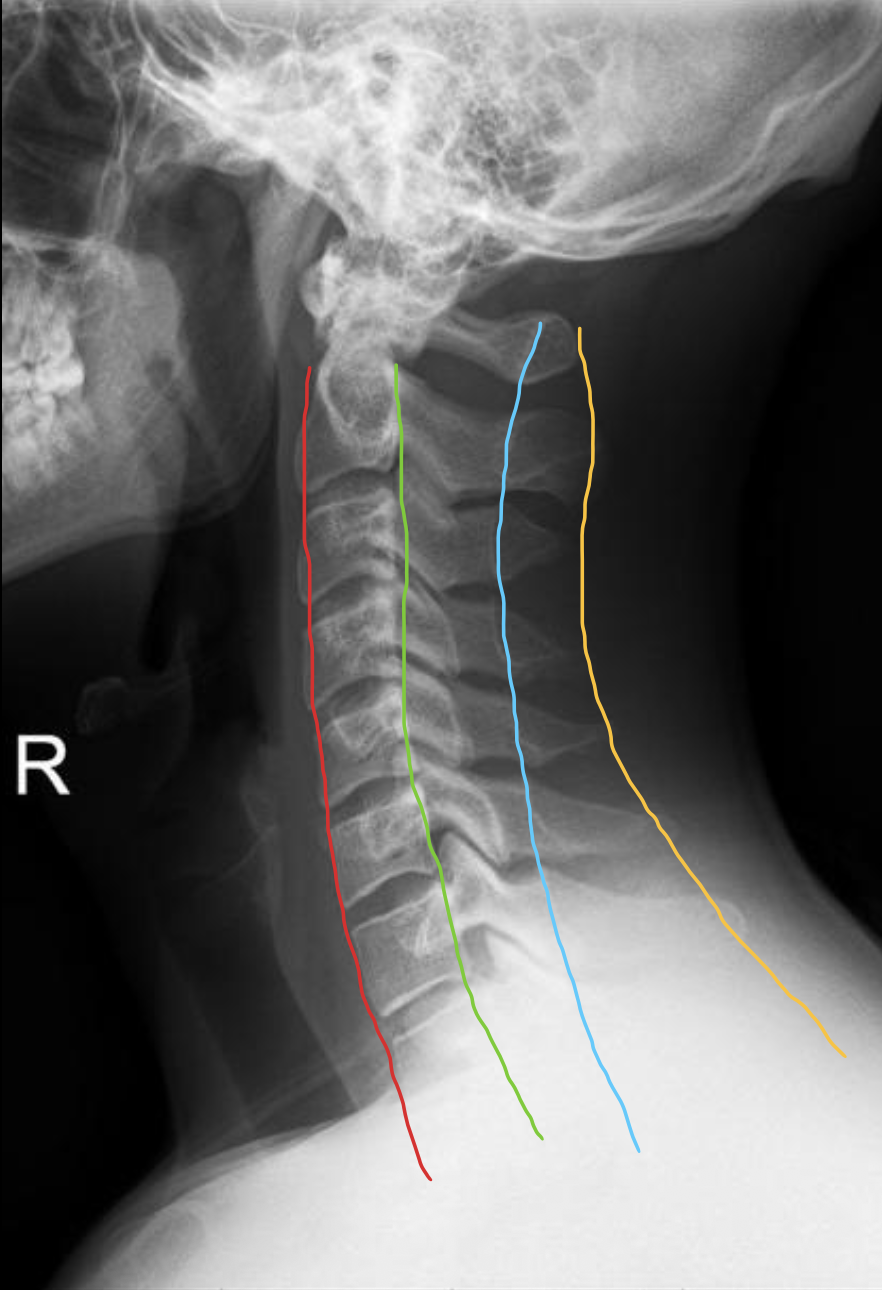

椎板棘突线(椎弓后缘线)

Spinolaminar

棘突后缘线

Posterior spinous

椎体

Vertebral body

寰椎前弓

Anterior arch of C1